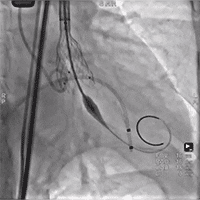

术中影像

瓣膜释放至2/3处造影